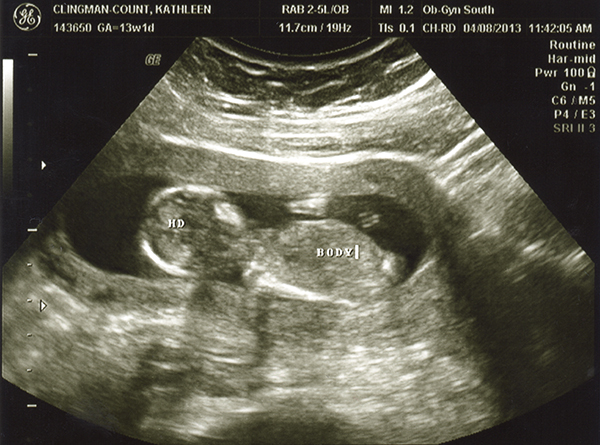

I had an ultrasound on Monday -- 13 weeks. I don't feel as though any of these are very clear pics. Even if they were better, I still wouldn't be any good with ultrasounds! Any of you experts able to make anything out with these? The tech guessed boy but the picture is not clear to me at all! She also kept saying the cord was between baby's legs and that we shouldn't go out and buy anything blue just yet. Any hope that it's a girl??

Attachment 10496